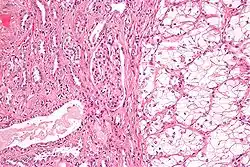

Generally, the cells have a clear cytoplasm, are surrounded by a distinct cell membrane and contain round and uniform nuclei.

Clear-cell renal-cell carcinoma. Macroscopy -

Clear-cell renal-cell carcinoma. HE, × 100 -